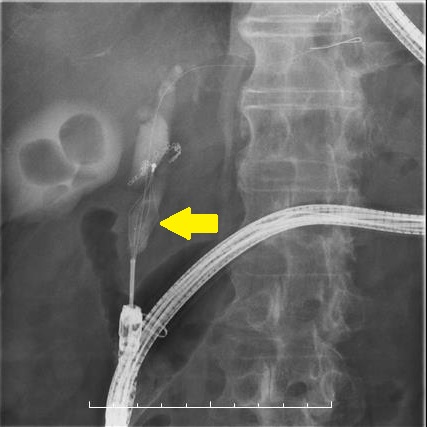

⑪ダブルバルーン内視鏡ERCP

1:十二指腸主乳頭をバルーンで拡張しています。

2:採石バスケットで総胆管結石を除去しています。

3:総胆管結石の除去に成功しました。

4:総胆管に結石を認めます(矢印)。

5:十二指腸主乳頭をバルーンで拡張しています(矢印)。

6:採石バスケットで総胆管結石を除去しています(矢印)。